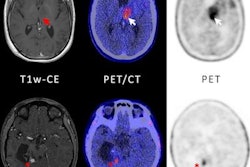

- A German team suggested PET imaging with an amino acid radiotracer (F-18 FET) can help guide treatment decisions in children with brain tumors.